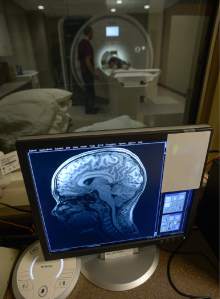

The director of the U.'s Cognitive Neuroimaging Laboratory wondered what similarities existed between the wartime traumas suffered by veterans and the head injuries suffered in sports. Finding athletes willing to participate in her research, however, wasn't always easy.

At the University of Utah, Yurgelun-Todd and her team are examining the impact of the combination of head trauma and other factors on the physical and mental health of the school's athletes.

The three-year study is tracking groups of football players, male basketball players, female basketball players, and a group of students who are not involved with athletics. The participants are evaluated twice a year — before and after their respective seasons — and undergo behavioral surveys and a trio of neuro-imaging scans.

"Many labs know how to do the things that we do, but not many labs do all the things that we do," Yurgelun-Todd said. "We have a multi-pronged approach to looking at the health of the brain."

"We're in the early phase of the study," she said. "We don't know enough yet. But we want to look at how the brain changes when it is exposed to the stress of being an athlete and also trauma, and create better time points and types of interventions."